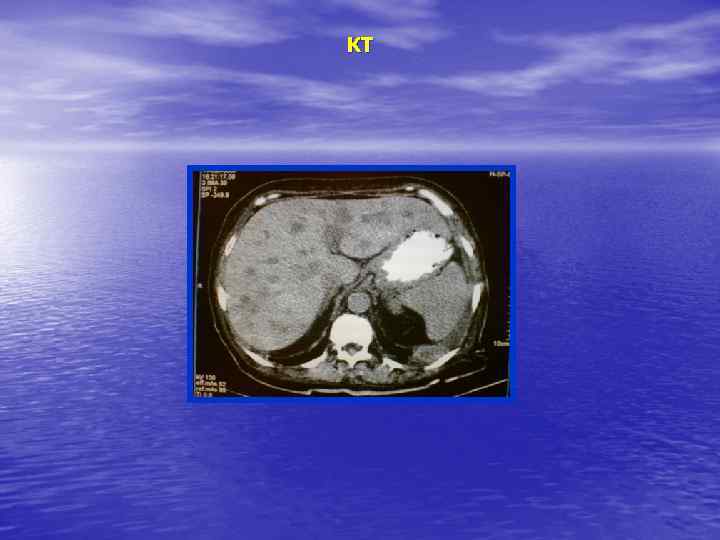

КТ-семиотика Диффузное поражение ВС- у в е л и ч е н и е печени МС – воспалительная инфильтрация, жировая дегенерация, гиперплазия

Очаговые поражения ВС: Увеличение печени, участок с измененной структурой паренхимы (гипо-, гиперденсивный, неоднородный). МС –объемное образование - опухоль, метастаз, эхинококковая киста

КТ-семиотика • Форма, размеры, положение, контуры • • • печени. Локализация участков поражения, их количество, денсивность (изо-, гипер-), форма, размеры, контуры, структура, состояние окружающих органов.